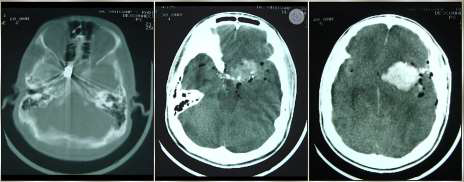

Paciente, 35 anos, sexo masculino, procedente de Recife-PE, é admitido em unidade de trauma, com história de agressão física por arma de fogo há 30 min. Veio trazido por policiais e sem profissional de saúde. Estava hipocorado, hipotérmico e possuía múltiplos orifícios de entrada de projétil de arma de fogo (PAF) em tórax, entrada e saída em região cervical e entrada em zigoma esquerdo. Apresentou parada cardiorrespiratória (PCR), revertida após 03 ciclos de reanimação cardiopulmonar, incluindo entubação orotraqueal sem sedação, expansão volêmica e drenagem torácica bilateral. Logo em seguida, após melhora hemodinâmica, não tinha abertura ocular e não tinha resposta motora, e pupilas estavam médio-fixas. De exame de imagem, fez apenas tomografia computadorizada (TC) de crânio.

Para o caso clínico mencionado acima, devem estar presentes os seguintes pré-requisitos para abertura de Protocolo de ME: